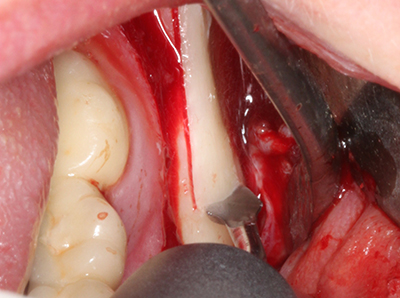

Si es preciso realizar intervenciones quirúrgicas en las que el hueso está en contacto directo con estructuras sensibles, como son los vasos sanguíneos o los nervios, los instrumentos rotativos presentan un enorme potencial de provocar lesiones iatrogénicas. Así, precisamente en la representación de nervios después de una lesión iatrogénica, o en el transcurso de la lateralización de un nervio para resecciones, reconstrucciones o incorporación de implantes, los equipos piezoeléctricos pueden resultar muy útiles para preparar la tapa ósea y retirar las partes de tejido duro cercanas al nervio (fig. 17-20). Por lo general, un ligero contacto del cordón nervioso con el inserto piezoeléctrico no tiene consecuencia alguna; ahora bien, un procedimiento poco cuidadoso con movimientos tipo sierra o piezas de trabajo sobre la base ósea aún existente puede provocar lesiones nerviosas temporales o incluso permanentes. Con todo, el riesgo de sufrir una lesión de este tipo se considera significativamente inferior que en los casos en los que se utilizan sierras y fresas (Pereira, Gealh et al. 2014).